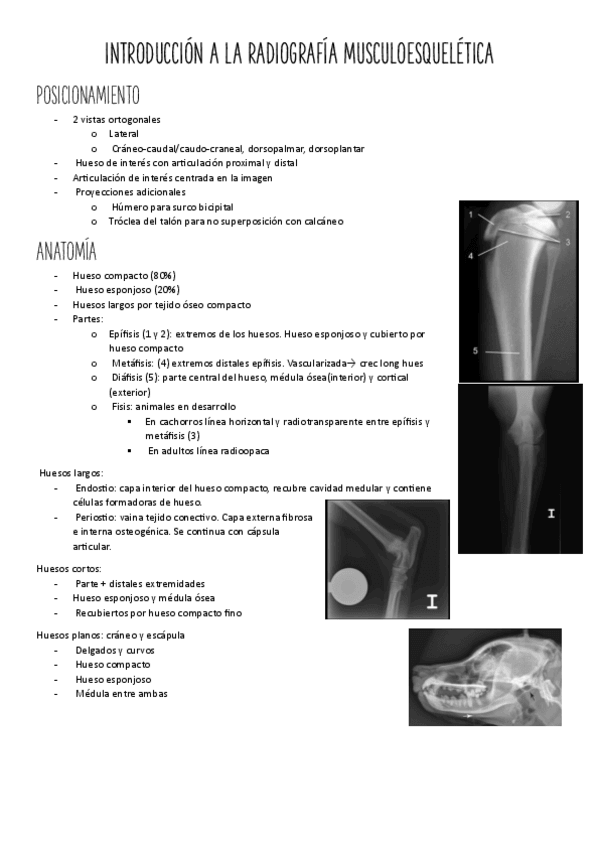

3.-Introduccion-a-la-radiografia-musculoesqueletica-y-columna.pdf